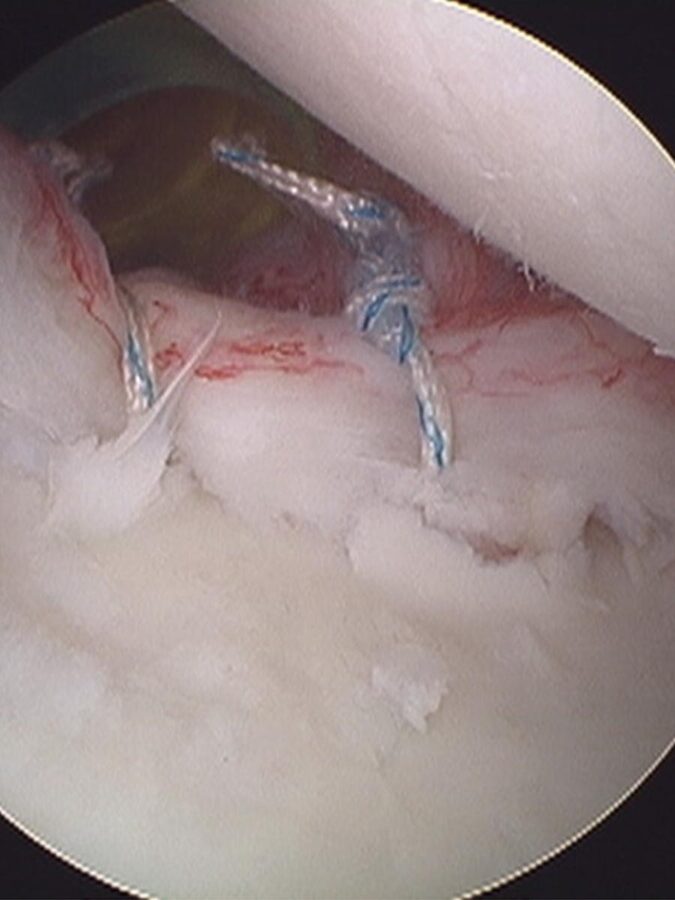

¿En que consiste la intervención? Mediante la artroscopia y la colocación de anclajes se reparan los ligamentos, así como el labrum.